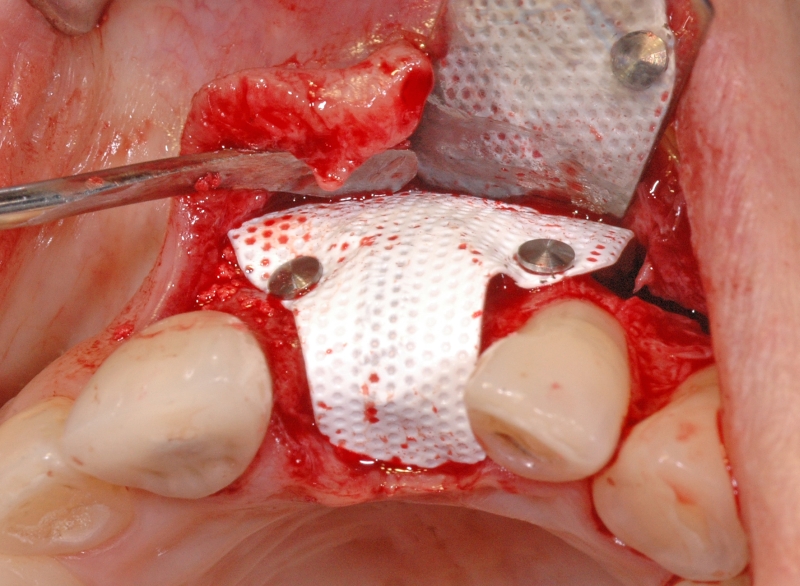

7/18 - Fixation of the membrane with titanitum pinsGBR together with soft tissue augmentation with mucoderm® and maxresorb® - Dr. S. Scherg